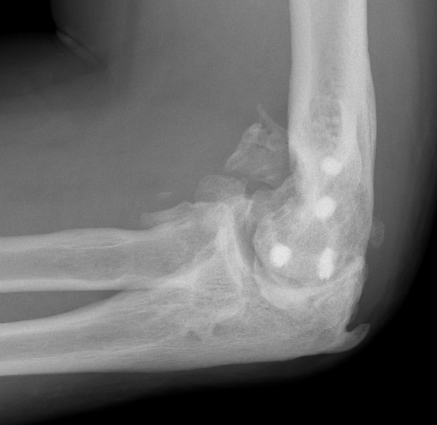

Xray

Elbow HOHOElbow Myositis Ossificans

HOHO

Radio-ulna synostosis

synostosissynostosis